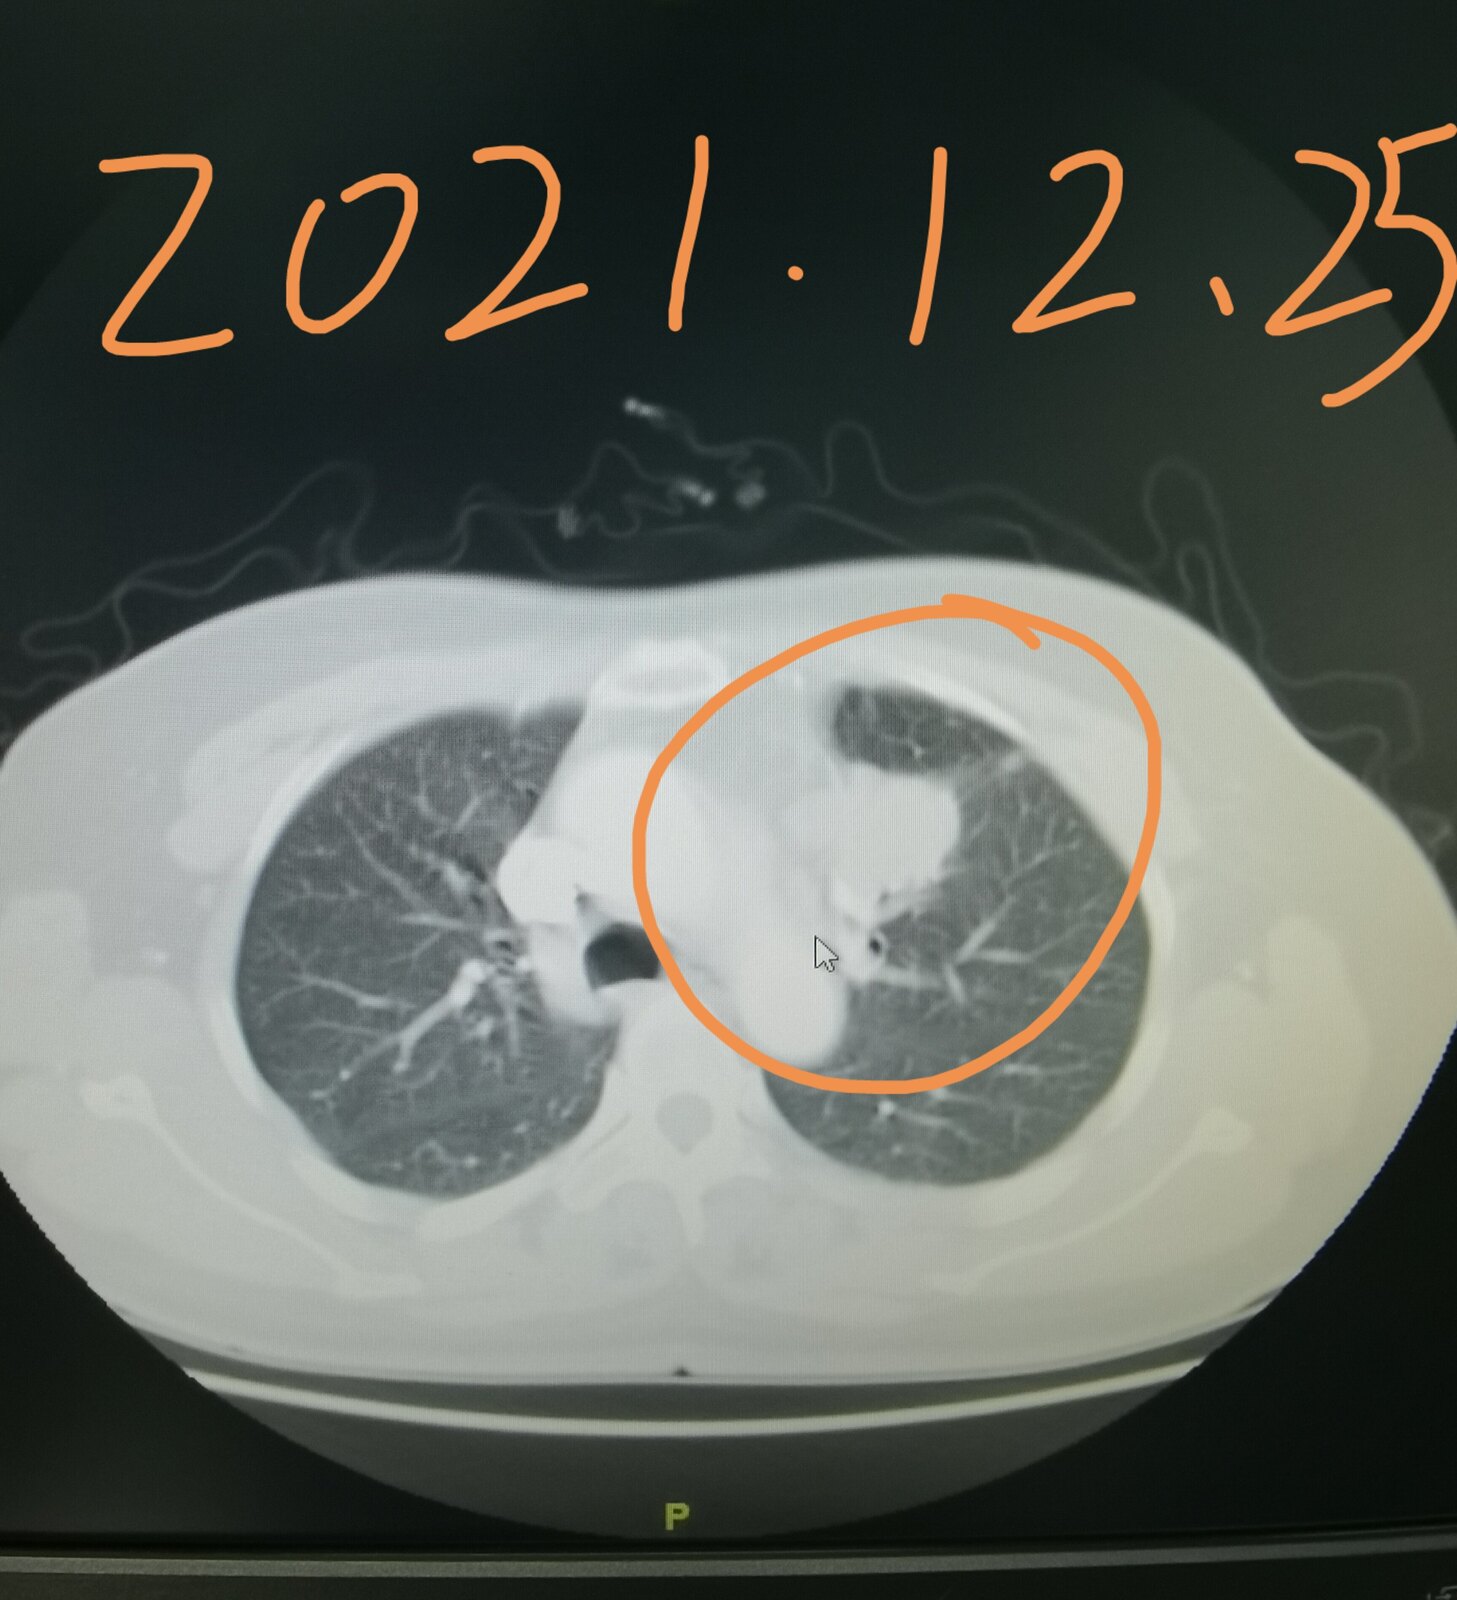

今天有一台手术就属于这个情况,我把这位患者的片子给大家发在下面,这是一位51岁的女士,三个月前因为咳嗽在当地医院拍片子,发现了肺部占位,她过来找我,想在我这里治疗。我给她进行了系统的检查,当时发现左上肺这个占位侵犯了纵隔,纵隔淋巴结增大,考虑转移,直接手术效果不好。这位女士好在其他部位并没有转移,我给她安排了穿刺,病理显示是一个肺腺癌,做基因检测,存在EGFR敏感突变,她吃了两个月的靶向药,肿瘤和淋巴结都缩小了。今天给她做的手术,手术过程是很困难的,里边粘连的比较严重,血管也很难分离,但过程很顺利,现在正在密切观察中。她除了左上肺这个病变之外,左下肺还有一个结节,吃靶向药也没有减小,术中探查的时候,考虑是一个肺内淋巴结,也给她一并切了下来。

通过这个病例我们知道,有些局部晚期肺癌,通过吃靶向药使肿瘤缩小,仍然有手术机会,并且效果会更好。